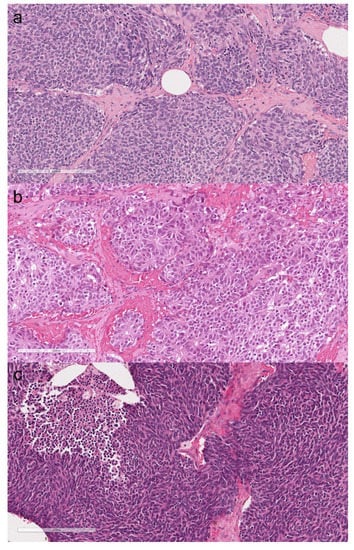

3.3. Thymic Neuroendocrine Tumors

3.4.2. Dedifferentiated Thymoliposarcoma

4.3. Thymic Neuroendocrine Tumors

4.4. Soft Tissue Thymic Tumors